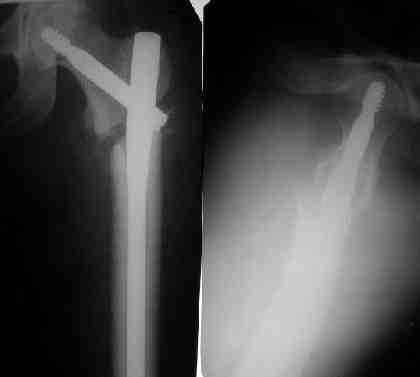

При межвертельных переломах с цефаломедуллярными гвоздями бывает, что проксимальый винт проходит или черед периферический отломок, или прямо над ним. И если остался диастаз, то этот винт при осевой нагрузке не дает сблизиться отломкам. Пример такого остеосинтеза в застарелом случае в приложении.

Картинка красивая, но на мой взгляд, не совсем оптимальная: Слишком медиально введён стержень - риск аваскулярного некроза головки бедра.

вариант межфрагментарного шинирования - зона достаточно простительная т.е. чрезвертельные переломы потенциально хорошо срастаются при любом

расположении сопредельных отломков- хорошая локальная васкуляризация. В приведённом случае я бы предпочёл принцип межфрагментарной компрессии (рекон/гамма нэйл 130- 135) принципу шинирования перелома.

Женя, эта картинка показывает не оптимальное лечение вертельных переломов в моем представлении, а особенности дизайна упомяутого фиксатора.

В частности, его возможности при фиксации переломов проксимального отдела бедра - в сравнении с другими, имеюшими лишь по одному статическому и динамическому отверстию и с кондуктором для введения 2 винтов.

Это было года 2,5 назад, мы тогда еще уточняли возможности шинирования с угловой стабильностью гвоздем с поперечным расположением винтов при переломах проксимального отдела бедра. Пациенту не пришлось приобретать намного более дорогой рекон или проксимальный гвоздь. В приложении еще несколько примеров применения того гвоздя при высоких переломах бедра, в том числе с более латеральной точкой входа. Гвоздь изгибаем для этого.